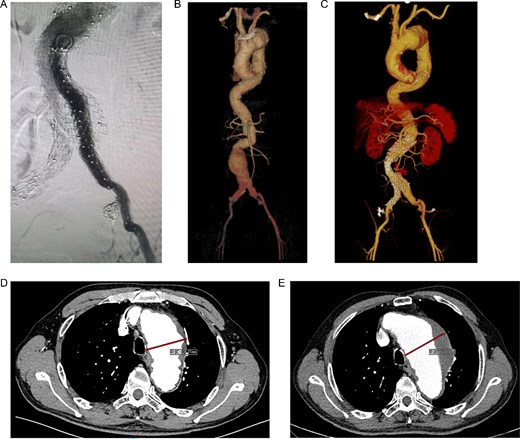

A 68-year-old male was admitted on July 14, 2023, with “intermittent blood in phlegm for over a month.” He had a history of EVAR and underwent right internal iliac aneurysm embolization (Fig. 1A) on July 18, 2019 for an abdominal aortic aneurysm (Fig. 1B). On July 1, 2022, he underwent left iliac artery stent graft implantation due to abdominal pain from a type Ib endoleak (see Fig. 1C). Computed tomography angiography (CTA) findings demonstrated that the maximum diameter of the thoracic aortic aneurysm had reached 72.64 mm and showed a 11.49 mm increase in aortic arch aneurysms over 3 years, which had been reached the established criteria for surgical intervention according to the 2022 ACC/AHA Guideline for the Diagnosis and Management of Aortic Disease [1] (Fig. 1D and E).

(A) Internal iliac artery embolization and stent graft implantation were performed. (B) Preoperative aortic CTA in 2019. (C) Type Ib endoleak from left iliac artery stent graft. (D) CTA shows the diameter of aortic arch aneurysm was 61.15 mm in July 2019. (E) CTA shows the diameter of aortic arch aneurysm was 72.64 mm in July 2022.